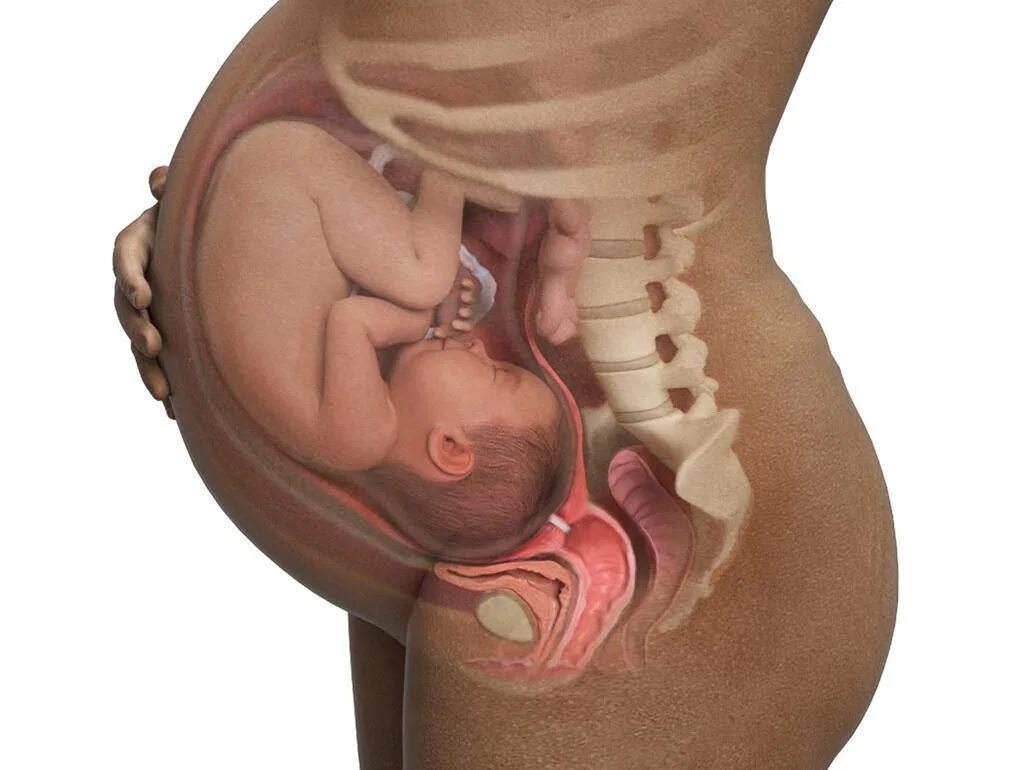

Большой плод при беременности